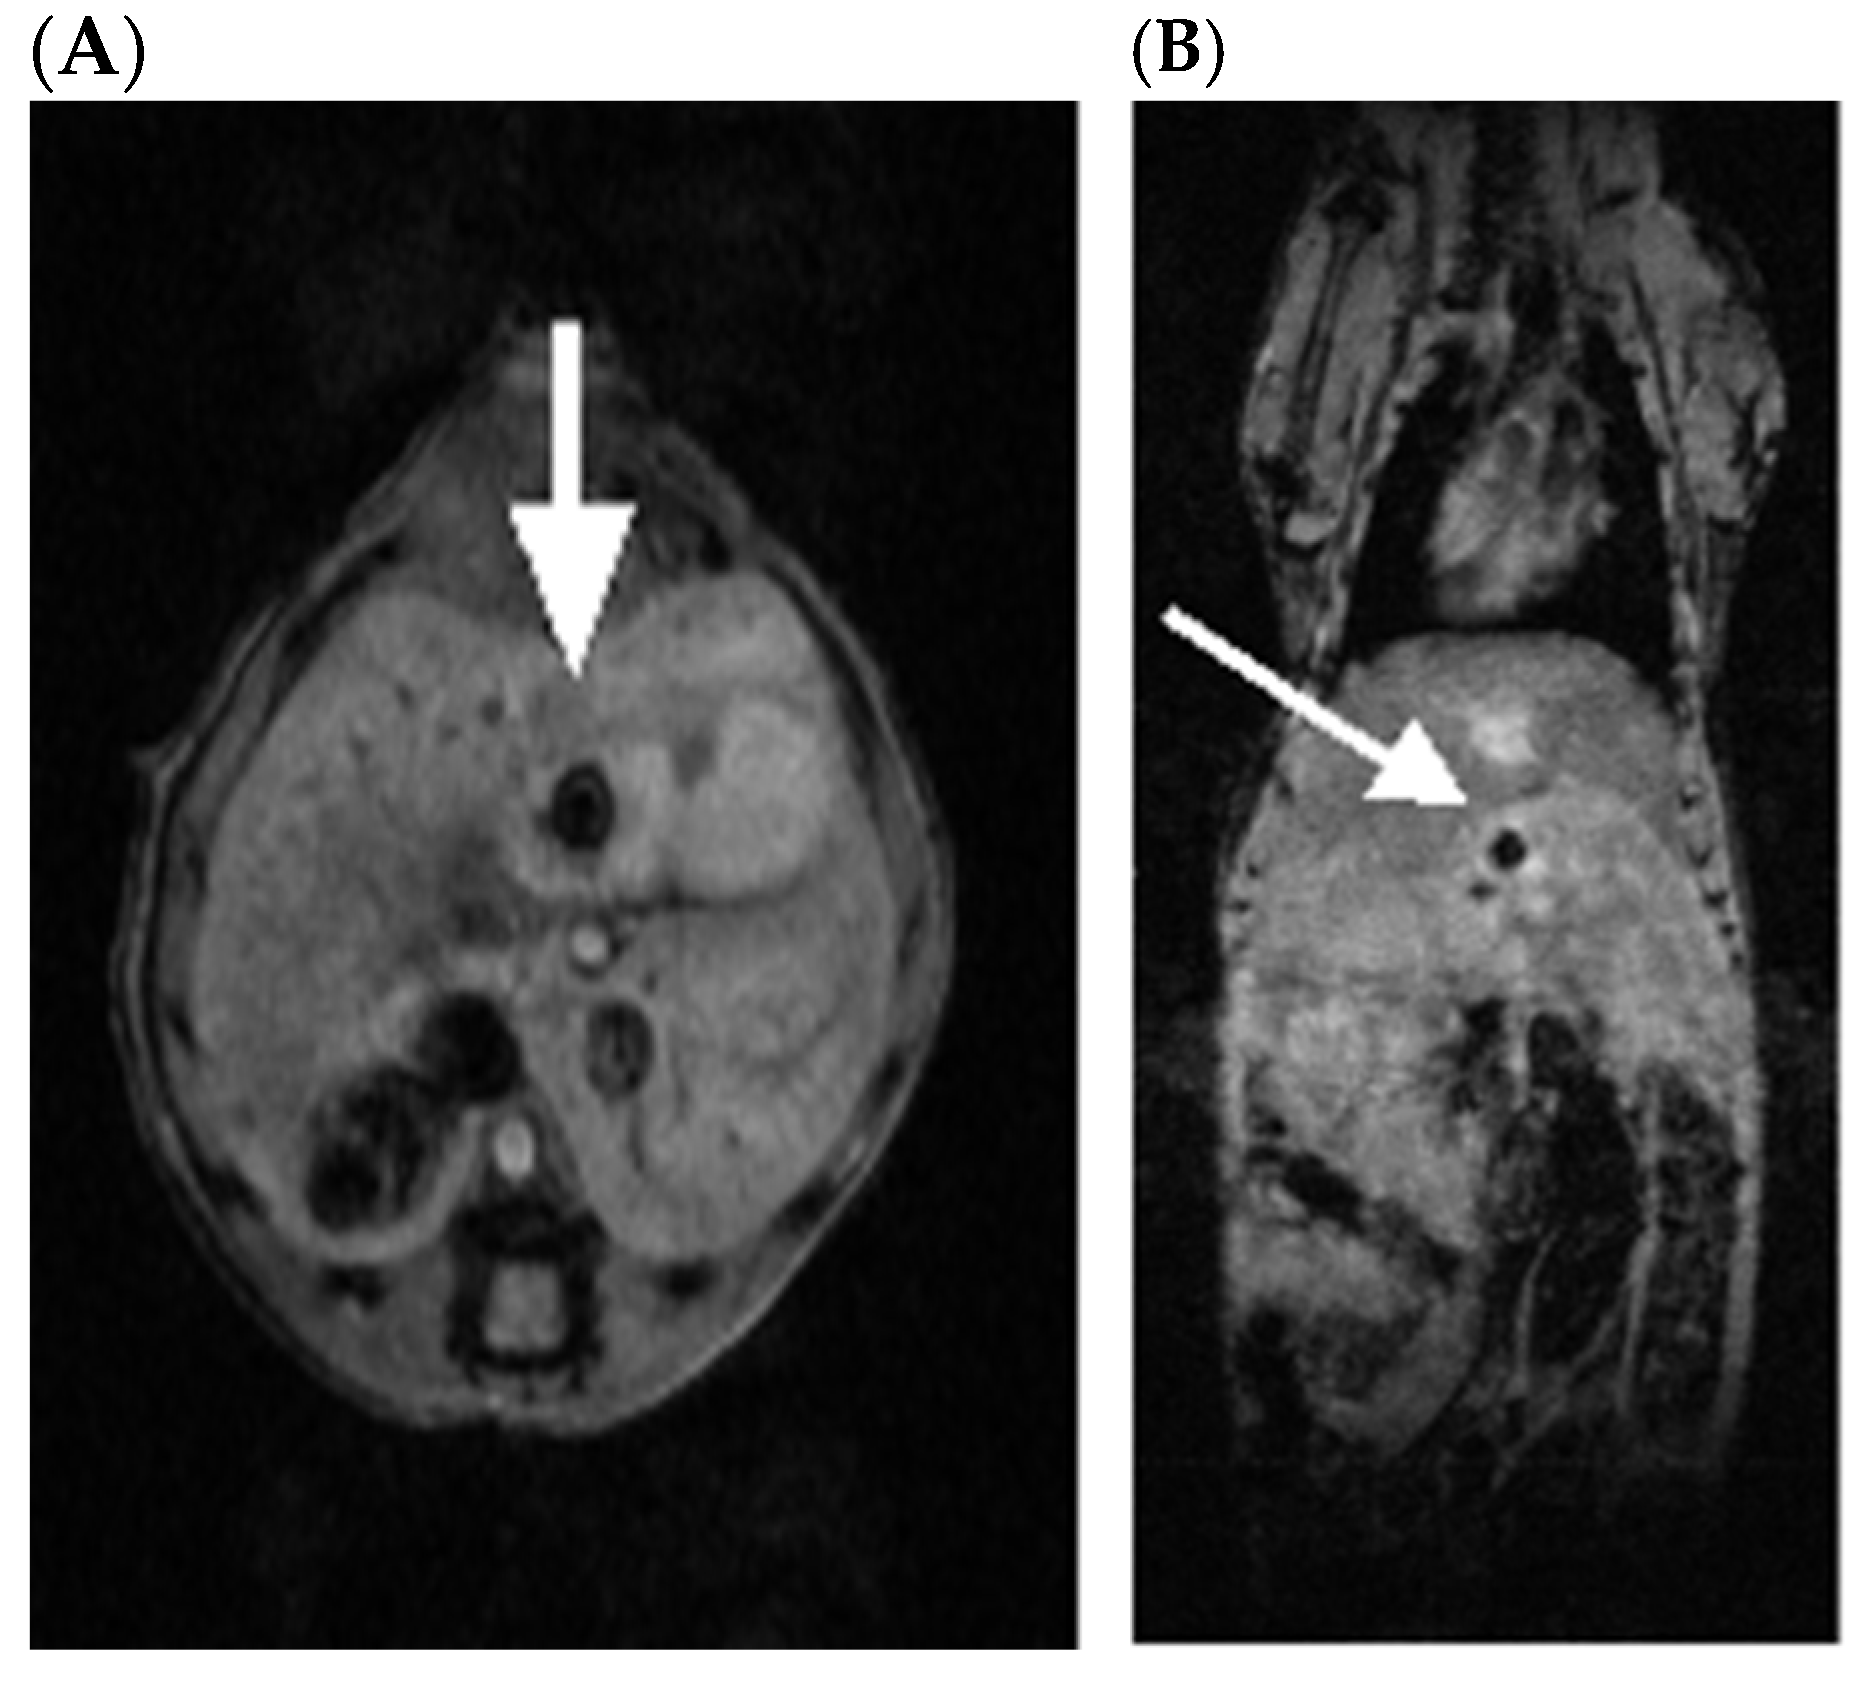

2.2. SV.IL-12 Can Reduce Metastasis in a Pan02 Syngeneic Mouse Model